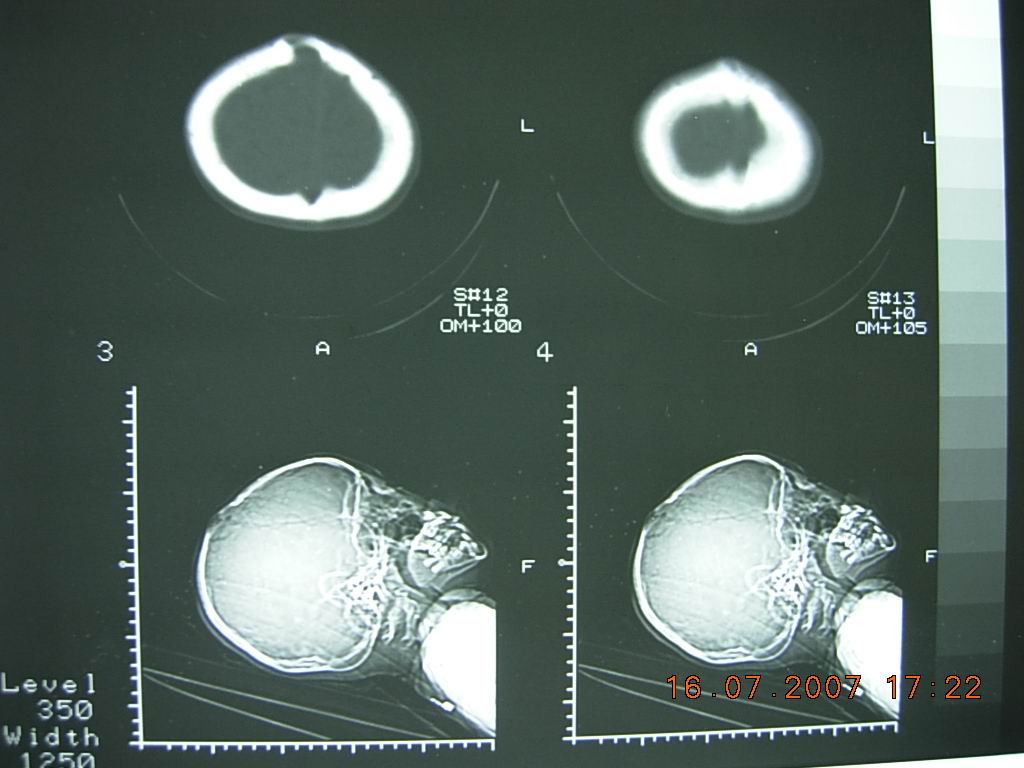

10岁女孩,家人十天前无意中发现顶部一硬的骨性突起,大小约3cm*4cm,无阳性临床症状。头颅ct如图所示。右顶骨内板骨质吸收消失,局部板障欠清,外板变薄呈局限性的轻度隆起,颅内脑实质未见异常征象。头皮软组织未见明显肿胀。考虑颅骨发育异常可能性大。请各位高人及同道指导,发表高见。

典型的顶骨大蛛网膜颗粒压迹。详见《中华放射学杂志》1994年第9期

chinese journal of radiology 起止页码:611-613国际标准刊号:issn 1005-1201国内统一刊号:cn 11-2149顶骨大蛛网膜颗粒迹:(附100例分析)

笔者分析100例顶骨大蛛网膜颗粒压迹,总发生率为19.8%,头颅正位片呈卵圆形或圆形骨质密度减低区,直径大于10mm,常位于顶前1/3区,对称分布于中线两侧、侧位或切线位呈弧形隆起,很象病理改变。

本例为右侧顶骨单发。

将上述杂志讨论部分简述如下:蛛网膜颗粒压迹大家已熟知,常位于中线两侧25-30mm 区内,直径2-4mm,圆或卵圆形骨质密度减低区,有的有引流静脉相连。

顶骨大于10mm的蛛网膜颗粒压迹,尚无专题报道,在临床实践中,常被误诊为病理改变,熟悉其特点,有利于鉴别诊断,避免不必要的检查。根据本组分析,特点如下;1、大的蛛网膜颗粒压迹以20岁以前多见,常因偶尔发现顶骨局限性隆起而就诊。2、头颅正位片呈卵圆形或圆形骨质密度减低区,对称分布于中线两侧,边缘清楚,上半部较硬,双侧大小各异。3、侧位片成弧形隆起,颅板变薄,重者内外板及板障分界不清,仅呈一致密弧线。4、弧形隆起常在冠状缝后方,极少跨越冠状缝。5、隆起的头皮组织正常。6、临近可见小蛛网膜颗粒压迹,但无异常血管沟。

正位片骨质密度减低,似颅骨病变,但切线位和侧位呈典型的颅板内压性改变,不同于颅骨嗜酸性肉芽肿,皮样或表皮样囊肿等病变所致的颅骨缺损,后者病变来源于板障,切线位片颅骨内外板分别向内外膨隆或翘起。脑凸面胶质瘤,脑外蛛网膜囊肿或硬膜内或外慢性血肿或水瘤都可压迫或侵蚀颅板,使其变薄,隆起或缺损,但大的蛛网膜颗粒压迹的部位和双侧对称分布,不同于前者。先天性顶孔很像顶骨大蛛网膜颗粒压迹,但前者是先天异常,位于顶后1/3区,双侧对称,大小各异,直径偶达数厘米,有导静脉通过,可触及骨缺损和波动。正位片呈圆或卵圆形缺损区,边缘锐利,无硬化,侧位或切线位呈局部颅板缺损,不是弧形隆起。

分析:本例侧位定位像表现典型,ct显示右侧改变,与报道者双侧多对称不同,但上述其他病变均可排除,诊断还是成立的。敬佩解放军总医院陈巨坤等对此征象的研究,到其发表时尚无专题报道。我94年就拜读此文,并应用于实践,注意观察,此征确实不少见。我认为应该属于正常变异。(发生率20%左右)